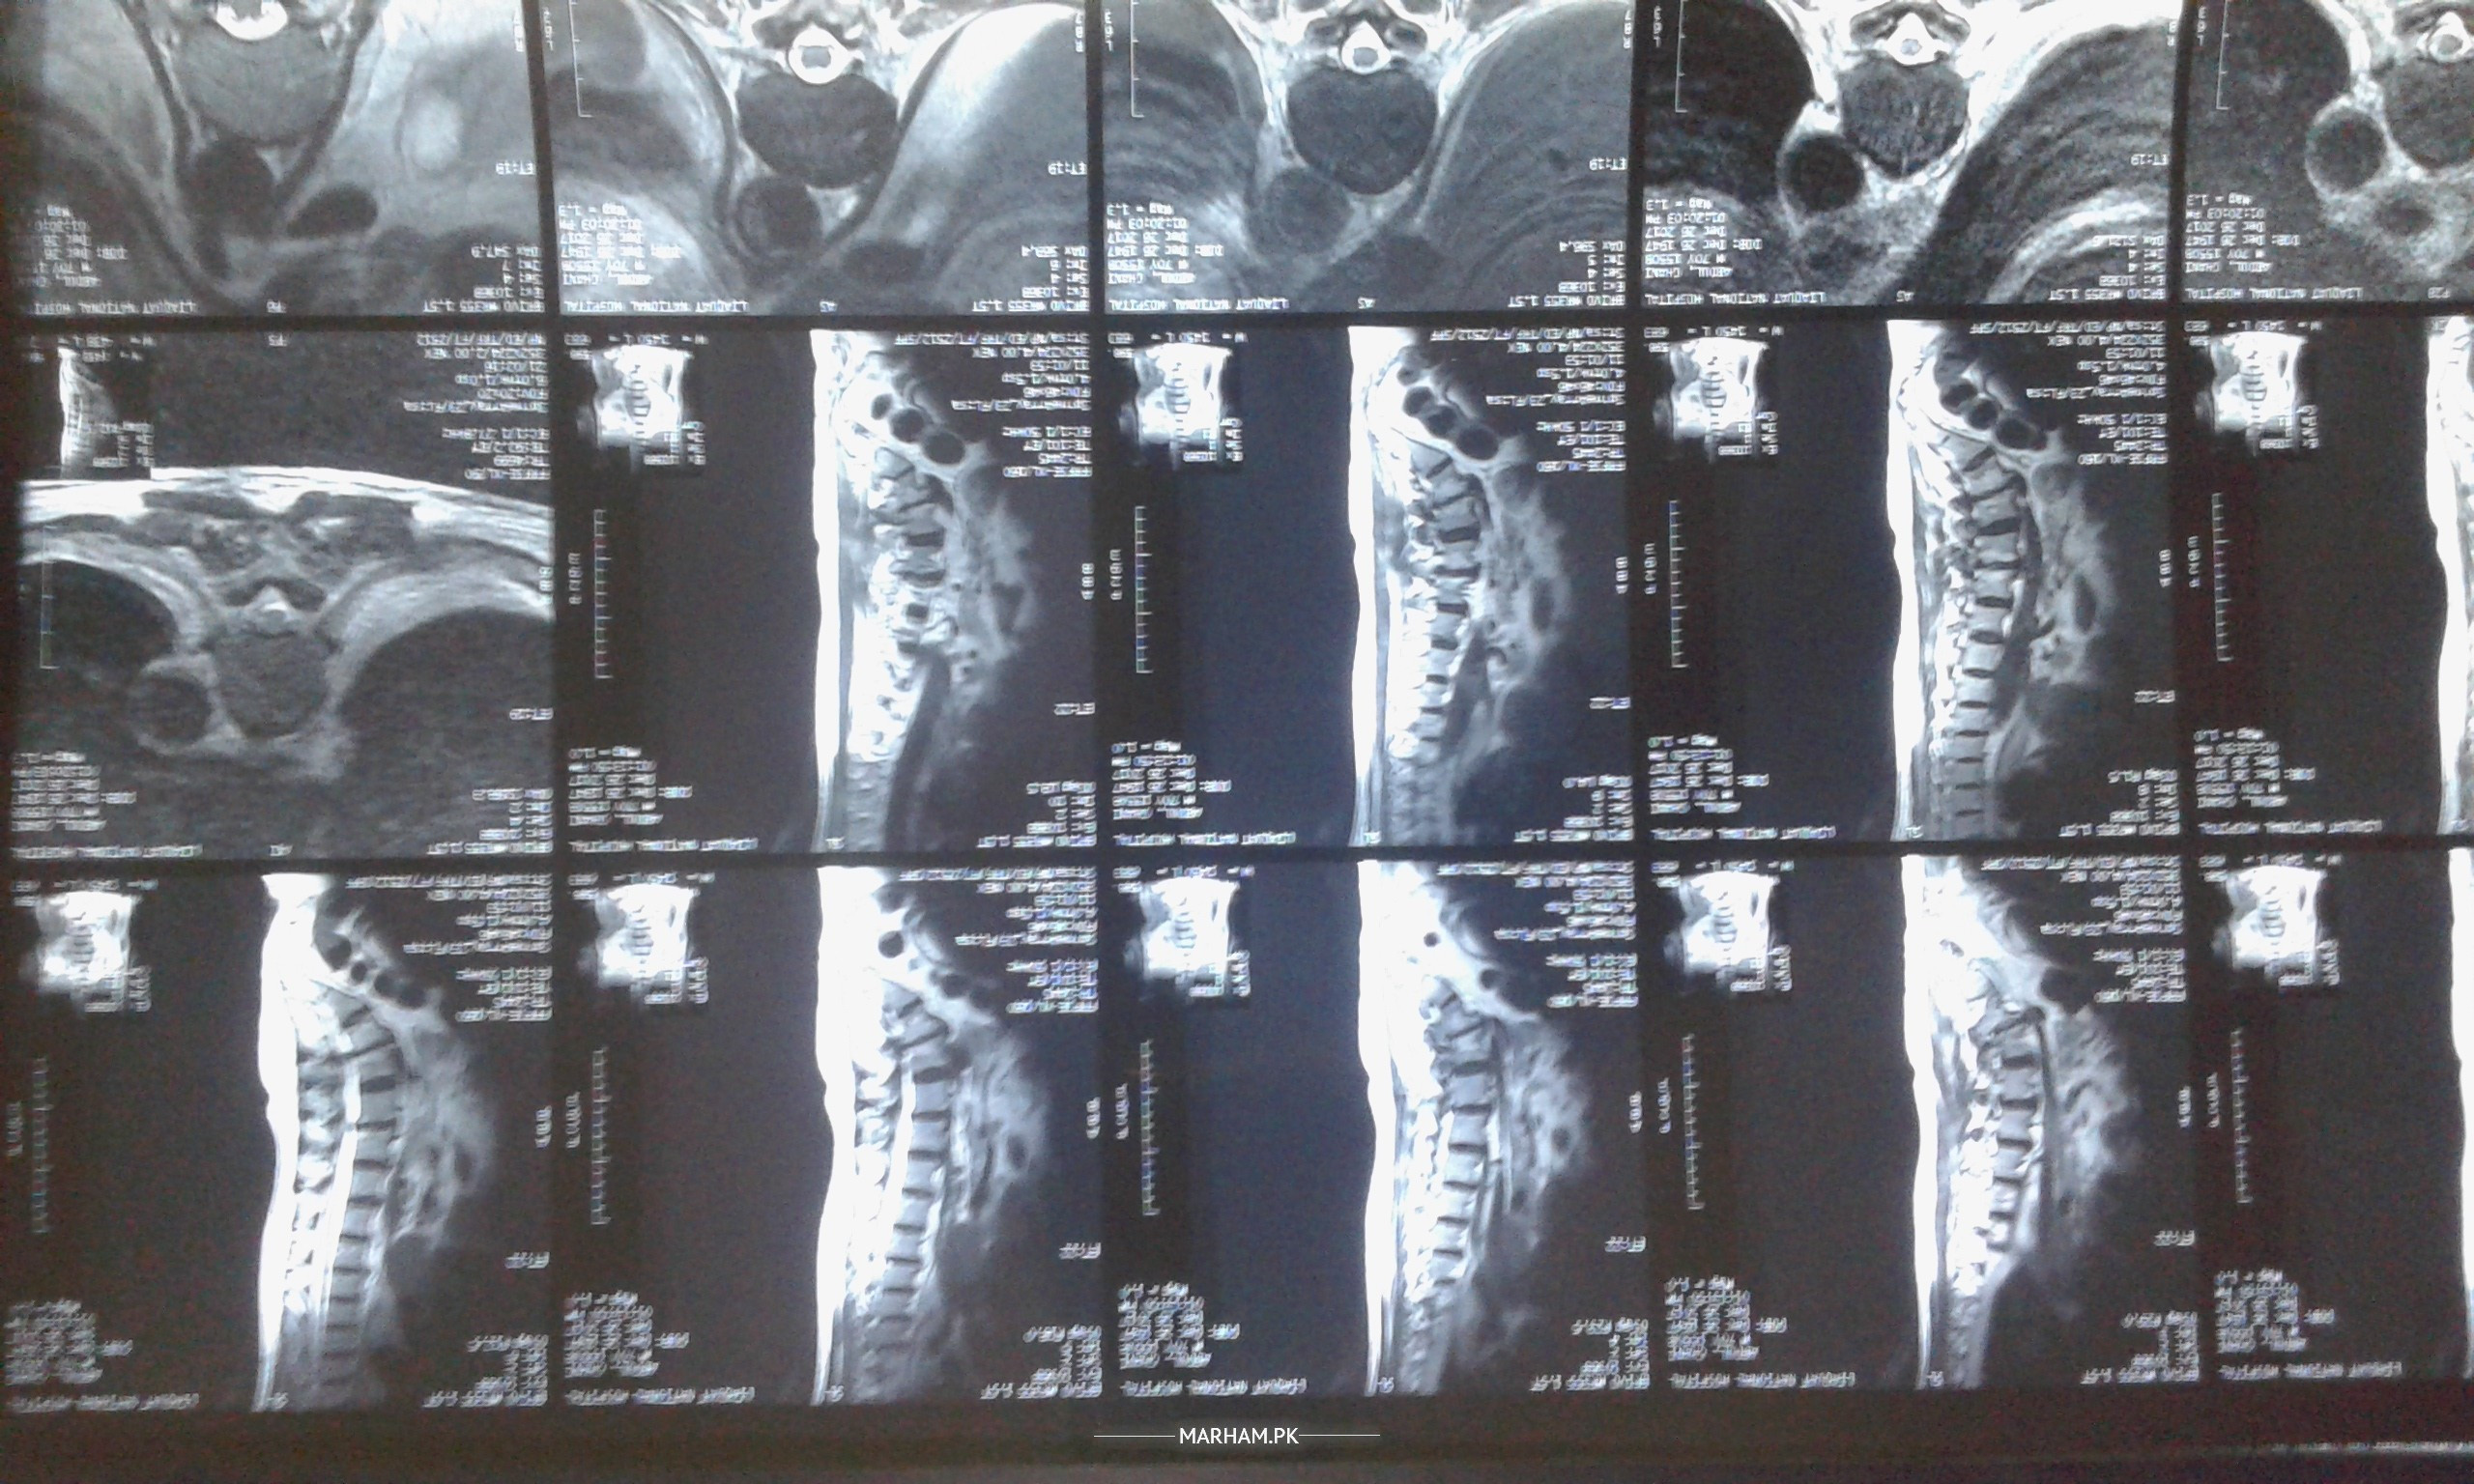

I am having a severe right leg pain starting from bottom till foot. Since my MRI report for Dorso Lumbar shows multi disc foraminal stenosis (report attached). Now I am wondering this pain might be result of pinching of sciatic nerve. Also, taking gabapentin and pregablin would help my nerve pain to be diminished?

Image attached as report! Many thanks!

Might not be very clear but I tried to upload the MRI film for my dorsolumbar.

Pics of MRI spinal is attached in the post above.